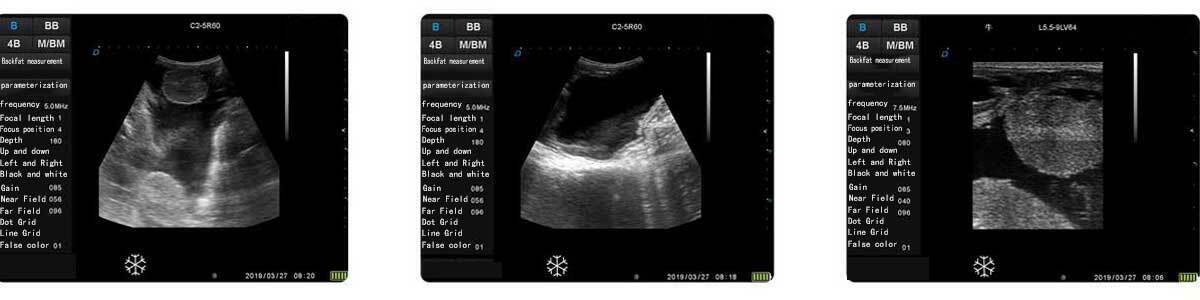

3.Powerful system functions

Display mode: B, BB, 4B, BM, M

Image optimization: 0-24

Permanent storage: 32G,TF card expandable

Total gain: 0-100

Support one-click full screen

Dynamic: 0-120

Movie playback: 255 frames

Brightness: 1-9 Pseudo-color: 28 kinds

Contrast: 1-9

Gamma correction adjustment: 0-9

Gray scale: 256 levels